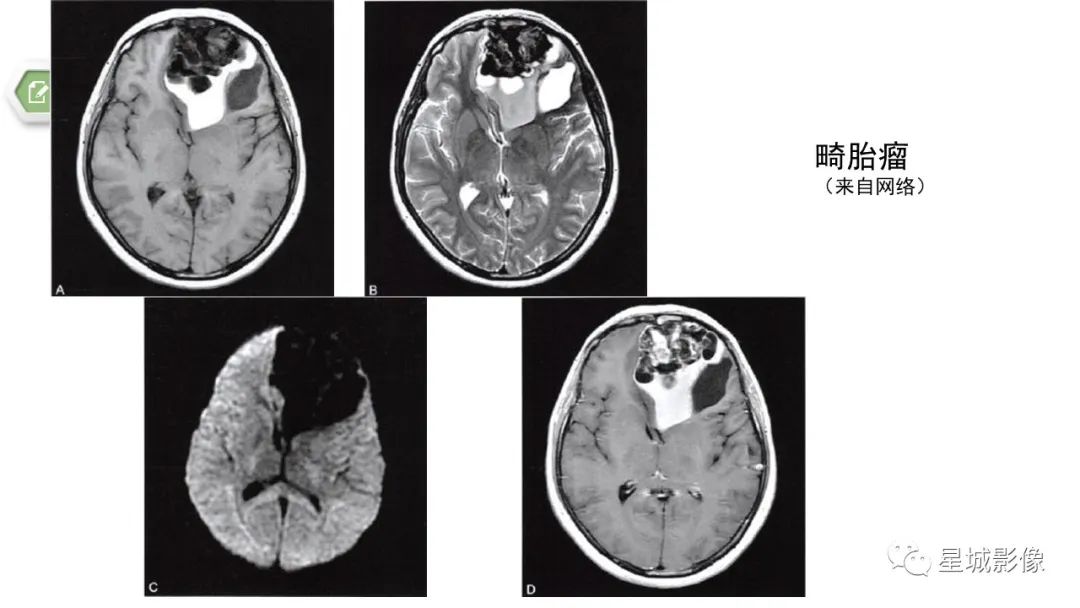

【病例】颅内成熟性囊性畸胎瘤1例MR影像表现-10

【病例】颅内成熟性囊性畸胎瘤1例MR影像表现-11

【病例】颅内成熟性囊性畸胎瘤1例MR影像表现-12